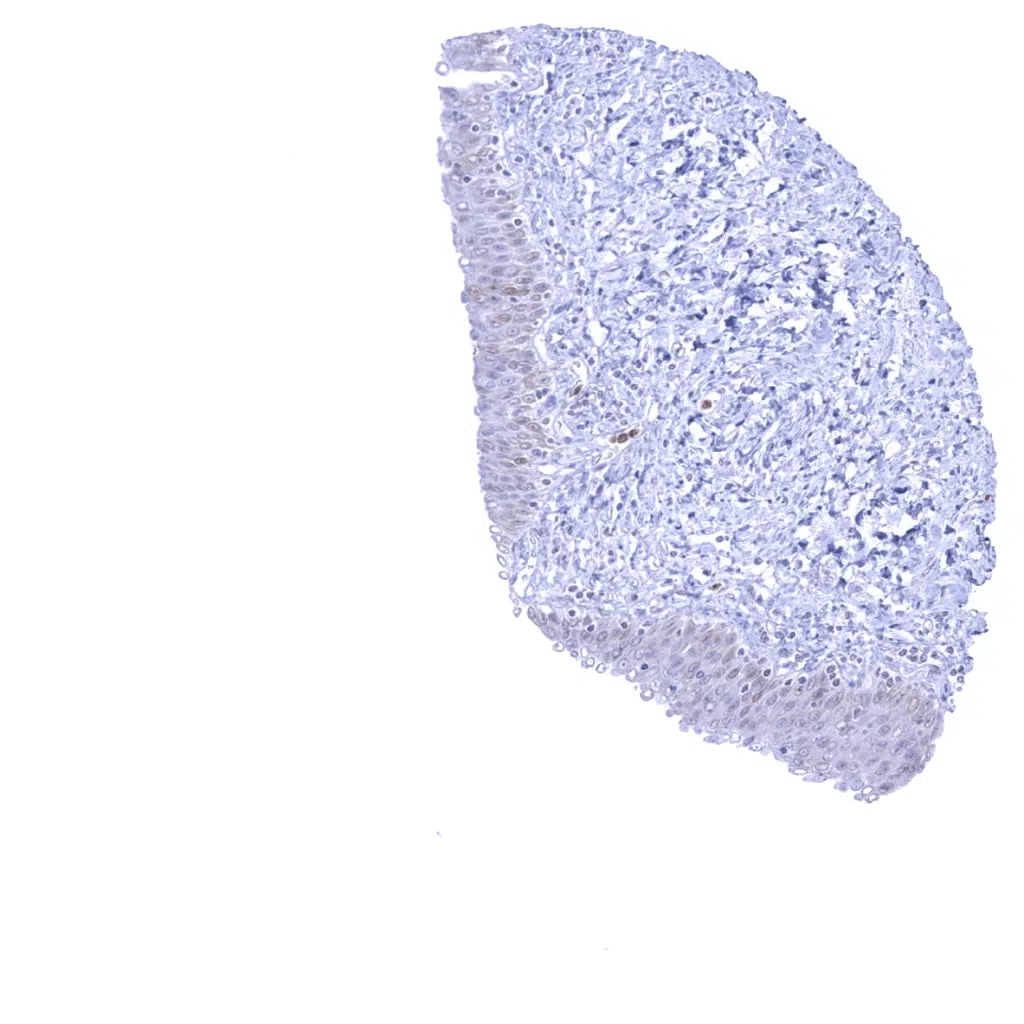

Tonsil - Strong Cystatin A immunostaining of crypt epithelium and of dendritic cells. Adjacent lymphocytes also show weak staining. This may represent a tissue contamination due to the very high levels of target protein in this tissue sample.